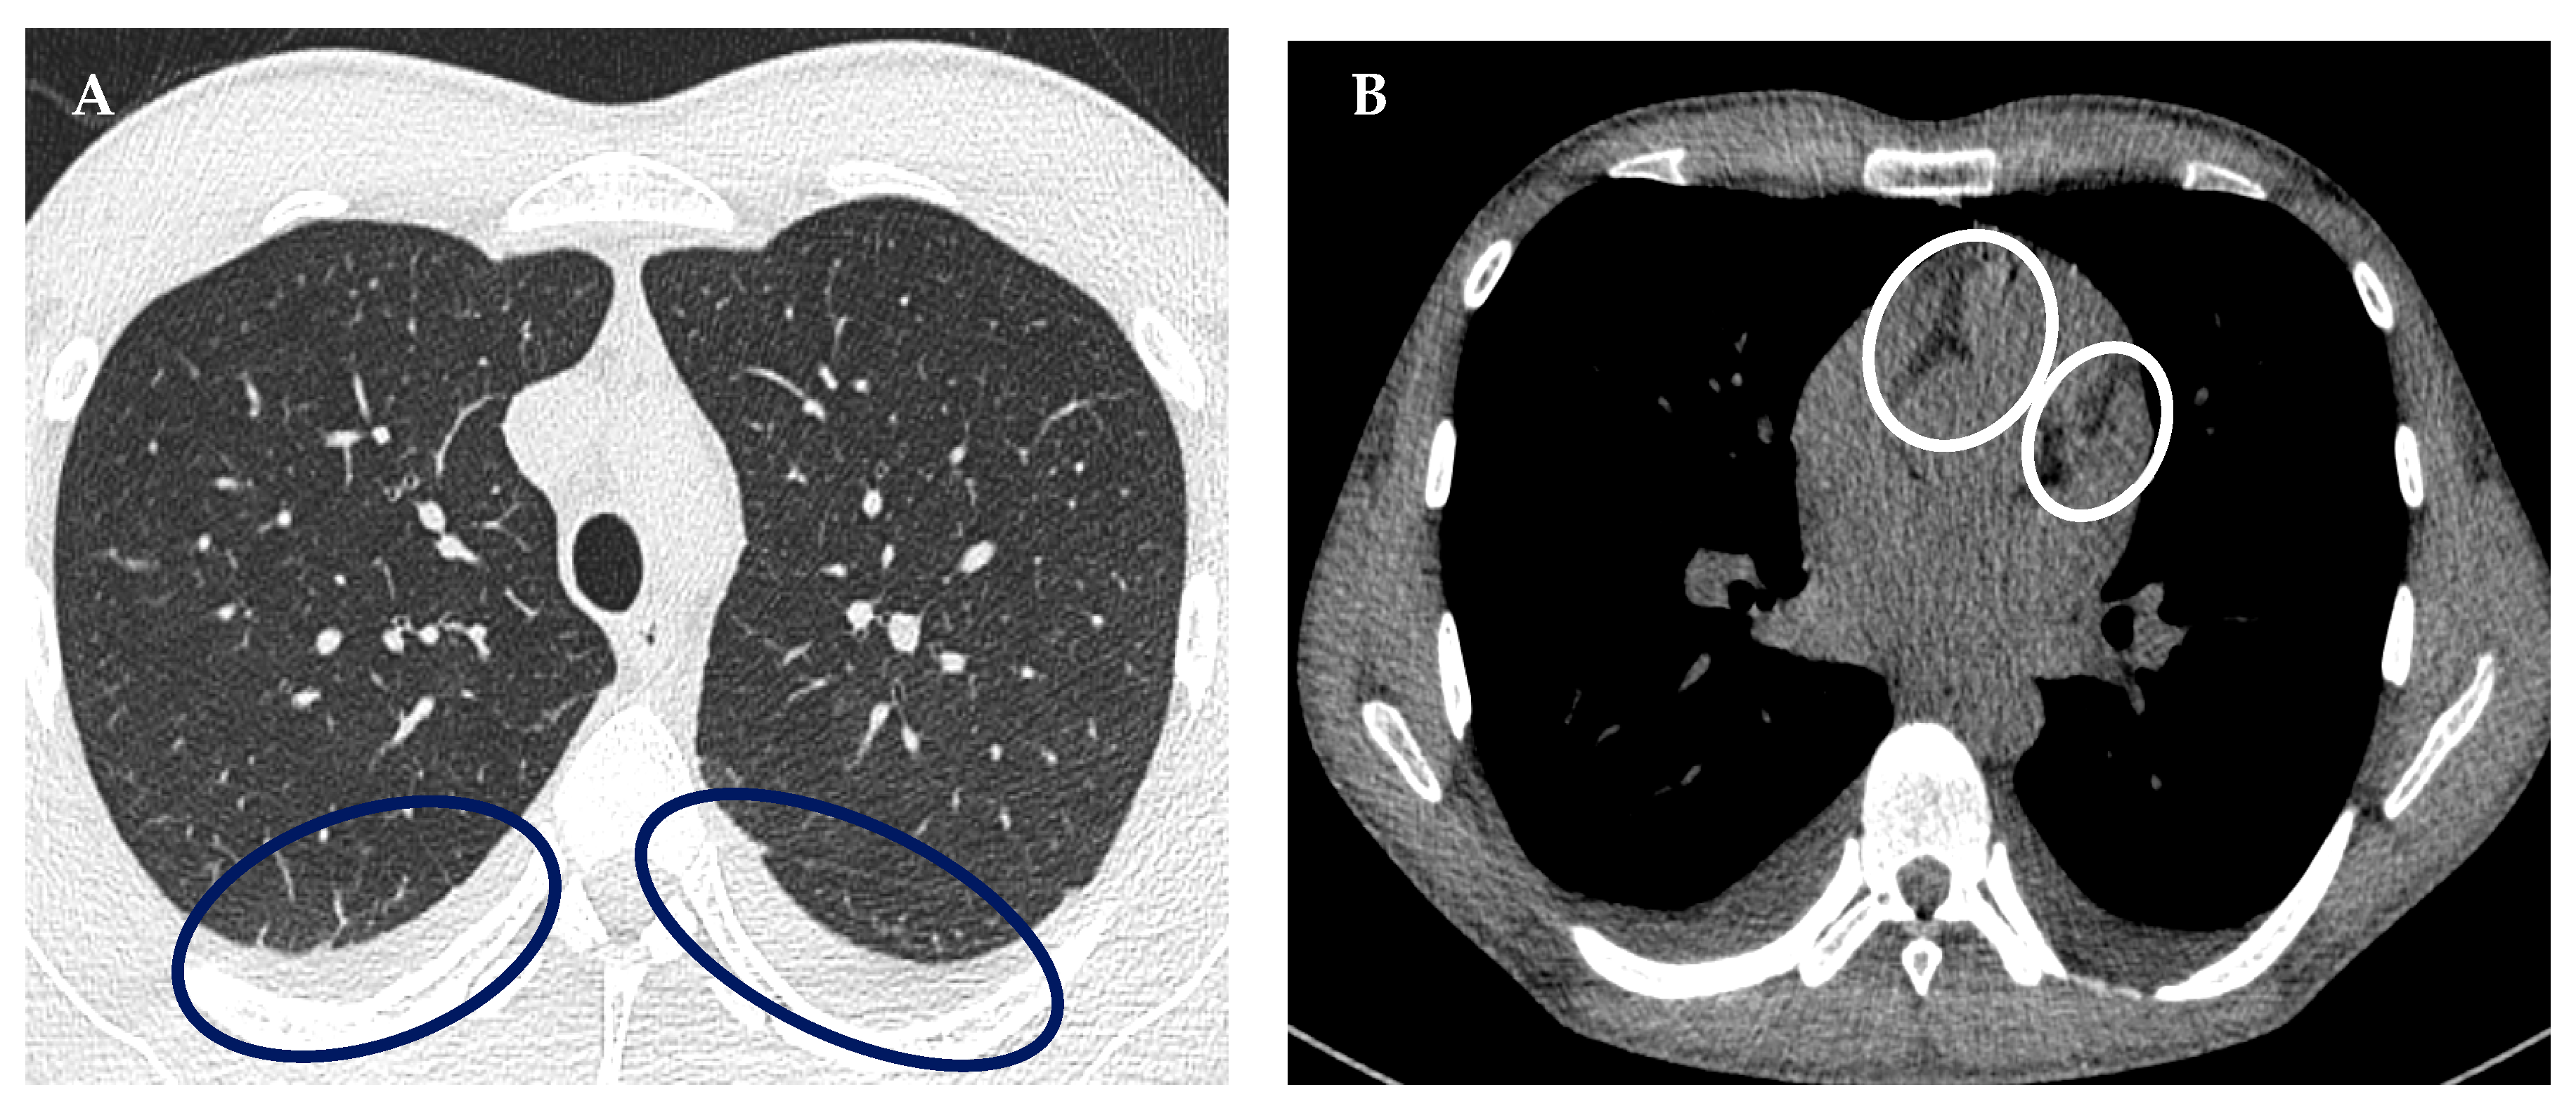

| Echocardiographic evidence of cardiac involvement or physical sigmata of heart failure | Pericardial effusion |